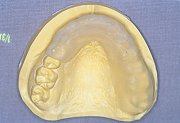

8

| 作業模型に装着していた直接法による前歯部スプリントを戻し、左右臼歯部にスプリントレジンLCを追加して、スタビライゼーションスプリントに移行した。 |